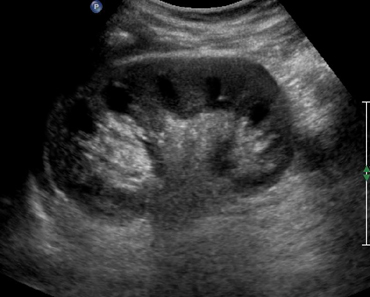

Для проведения УЗИ брюшных органов пациент принимает горизонтальное положение на спине, врач может попросить его сделать глубокий вдох или выдох, принять удобное положение на левом/правом боку.

Данное обследование поможет выявить заболевания, связанные с нарушением работы печени, желудка, поджелудочной железы, почек, селезенки, желчного пузыря и протоков и т. д. Врач может назначить как обследование 1 органа, если известно, что именно беспокоит, так и полное комплексное изучение всех органов ЖКТ.

Исключение составляют только кишечник и зона 12-перстной кишки, так как они имеют практически не проходимую для ультразвука структуру.